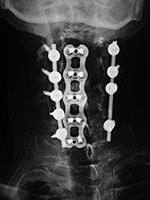

Odontoid Fracture Fixation

Type III dens fracture Den fracture fixation device for fusion occiput-C2 Dens fracture fixation from occiput to C2 Dens fracture fixation from occiput to C2

47 year-old woman with type III dens fracture treated by occiput-C2 fusion.